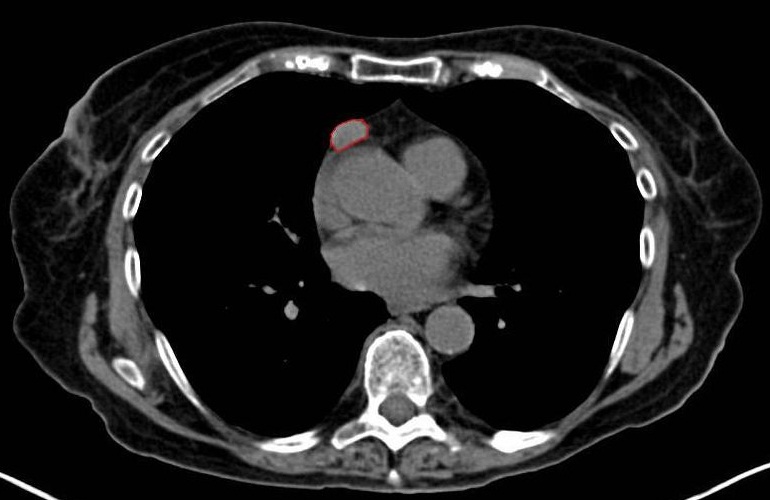

Nanoporphyrine werden die Nanopartikel genannt, die unter anderem gezielt Wirkstoffe in die Krebszellen transportieren können. Das Funktionsspektrum der neuen Hightech-Armee gegen den Krebs ist dabei vielfältig. Schließlich sind die intelligenten und mikroskopisch kleinen Partikel auch in der Lage Informationen über das Wachstum der Karzinome einzuholen und diese für die Analyse entsprechend aufzubereiten. Die Behandlung von Krebs wird somit auf ein neues und effizienteres Level gehoben, was zuletzt von einem Großteil der Menschheit befürwortet werden dürfte. Den Krebs gezielt bekämpfen zu können ist eine große Herausforderung, die Forscher schon seit Jahrzehnten zu perfektionieren versuchen. Die Nanobots kommen dem gesetzten Ziel schon sehr nahe, so dass auch in diesem Bereich der Forschung große Hoffnungen gehegt werden können.